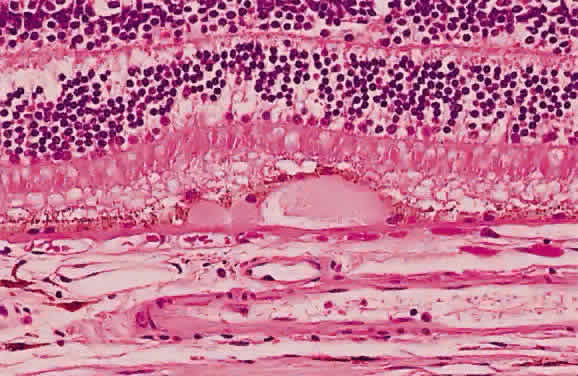

and has sharp borders (Fig. 13).  Fig. 11. A. Section of retina with hemorrhage in the nerve fiber layer (between the two large arrows). Notice that the limits of the hemorrhage are not clearly defined, since

scattered red blood cells can be seen to the right of the right-hand

large arrow. This histologic picture corresponds to a clinically observed

fame-shaped hemorrhage with an indistinct border. The detached

posterior hyaloid is marked by four small arrows. B. Fundus photograph of nerve fiber layer hemorrhage. They are oriented parallel

to the plane of the internal limiting membrane. Because of their

dispersal within the ganglion cell layer, the borders are “feathery” (flame

shaped). Fig. 11. A. Section of retina with hemorrhage in the nerve fiber layer (between the two large arrows). Notice that the limits of the hemorrhage are not clearly defined, since

scattered red blood cells can be seen to the right of the right-hand

large arrow. This histologic picture corresponds to a clinically observed

fame-shaped hemorrhage with an indistinct border. The detached

posterior hyaloid is marked by four small arrows. B. Fundus photograph of nerve fiber layer hemorrhage. They are oriented parallel

to the plane of the internal limiting membrane. Because of their

dispersal within the ganglion cell layer, the borders are “feathery” (flame

shaped).